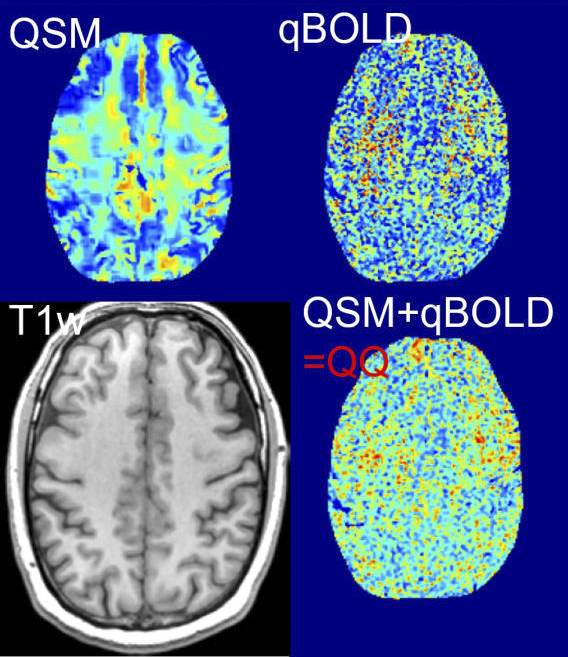

To obtain an accurate OEF map, we are developing realistic biophysics models based on MR physics. For instance, our recent model, namely QQ, considers deoxyhemoglobin effect, i.e. OEF effect, on MRI phase signal using quantitative susceptibility mapping (QSM) and magnitude signal using quantitative blood oxygen level dependent magnitude (qBOLD). QQ can estimate OEF using a single routine MRI sequence without impractical vascular challenges unlike the other methods, which provides a high potential in clinical use.

See our recent work on an integrative OEF model, QSM+qBOLD=QQ